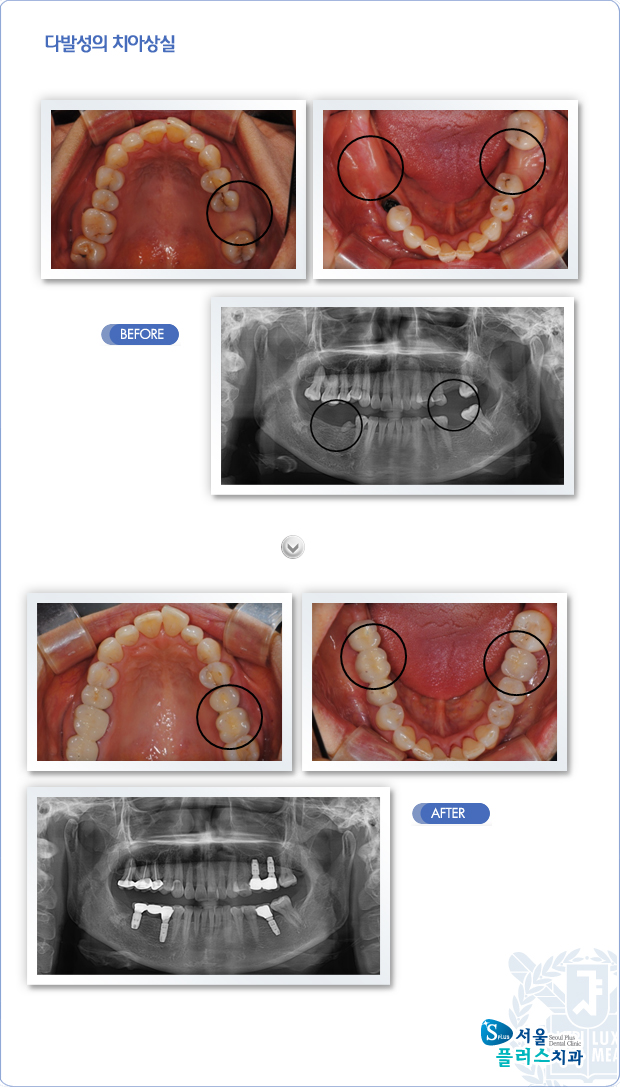

[임플란트] 다발성의 치아상실